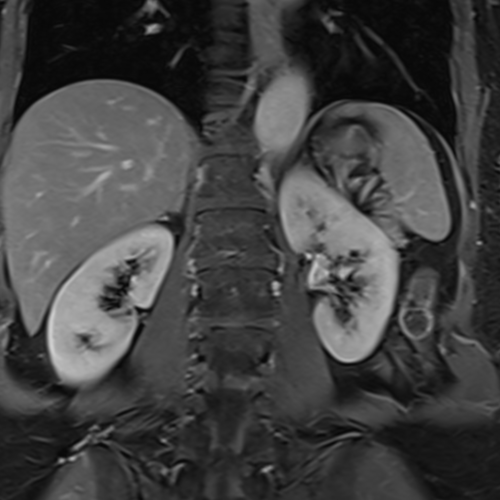

Cet examen est réalisé pour analyser le reins et les surrénales.

Cette examen permets d’analyser le parenchyme rénale et des surrénales. Il permet de diagnostiquer les cancers, adénocarcinomes des reins, les kystes qui sont classés selon Bosniak, tumeurs papillaires, carcinomes a cellules claires.